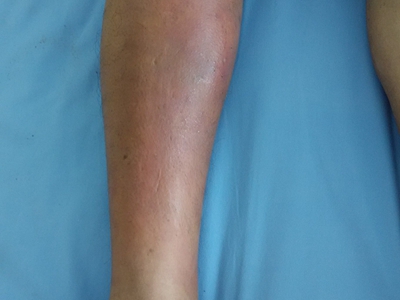

严重中毒者可迅速出现昏迷、呼吸抑制、肺水肿、心律失常或心力衰竭,表现为皮肤苍白。病人可呈去皮质综合征状态。部分病人合并吸入性肺炎。受压部位皮肤可出现红肿和水疱。眼底检查可发现视盘水肿。